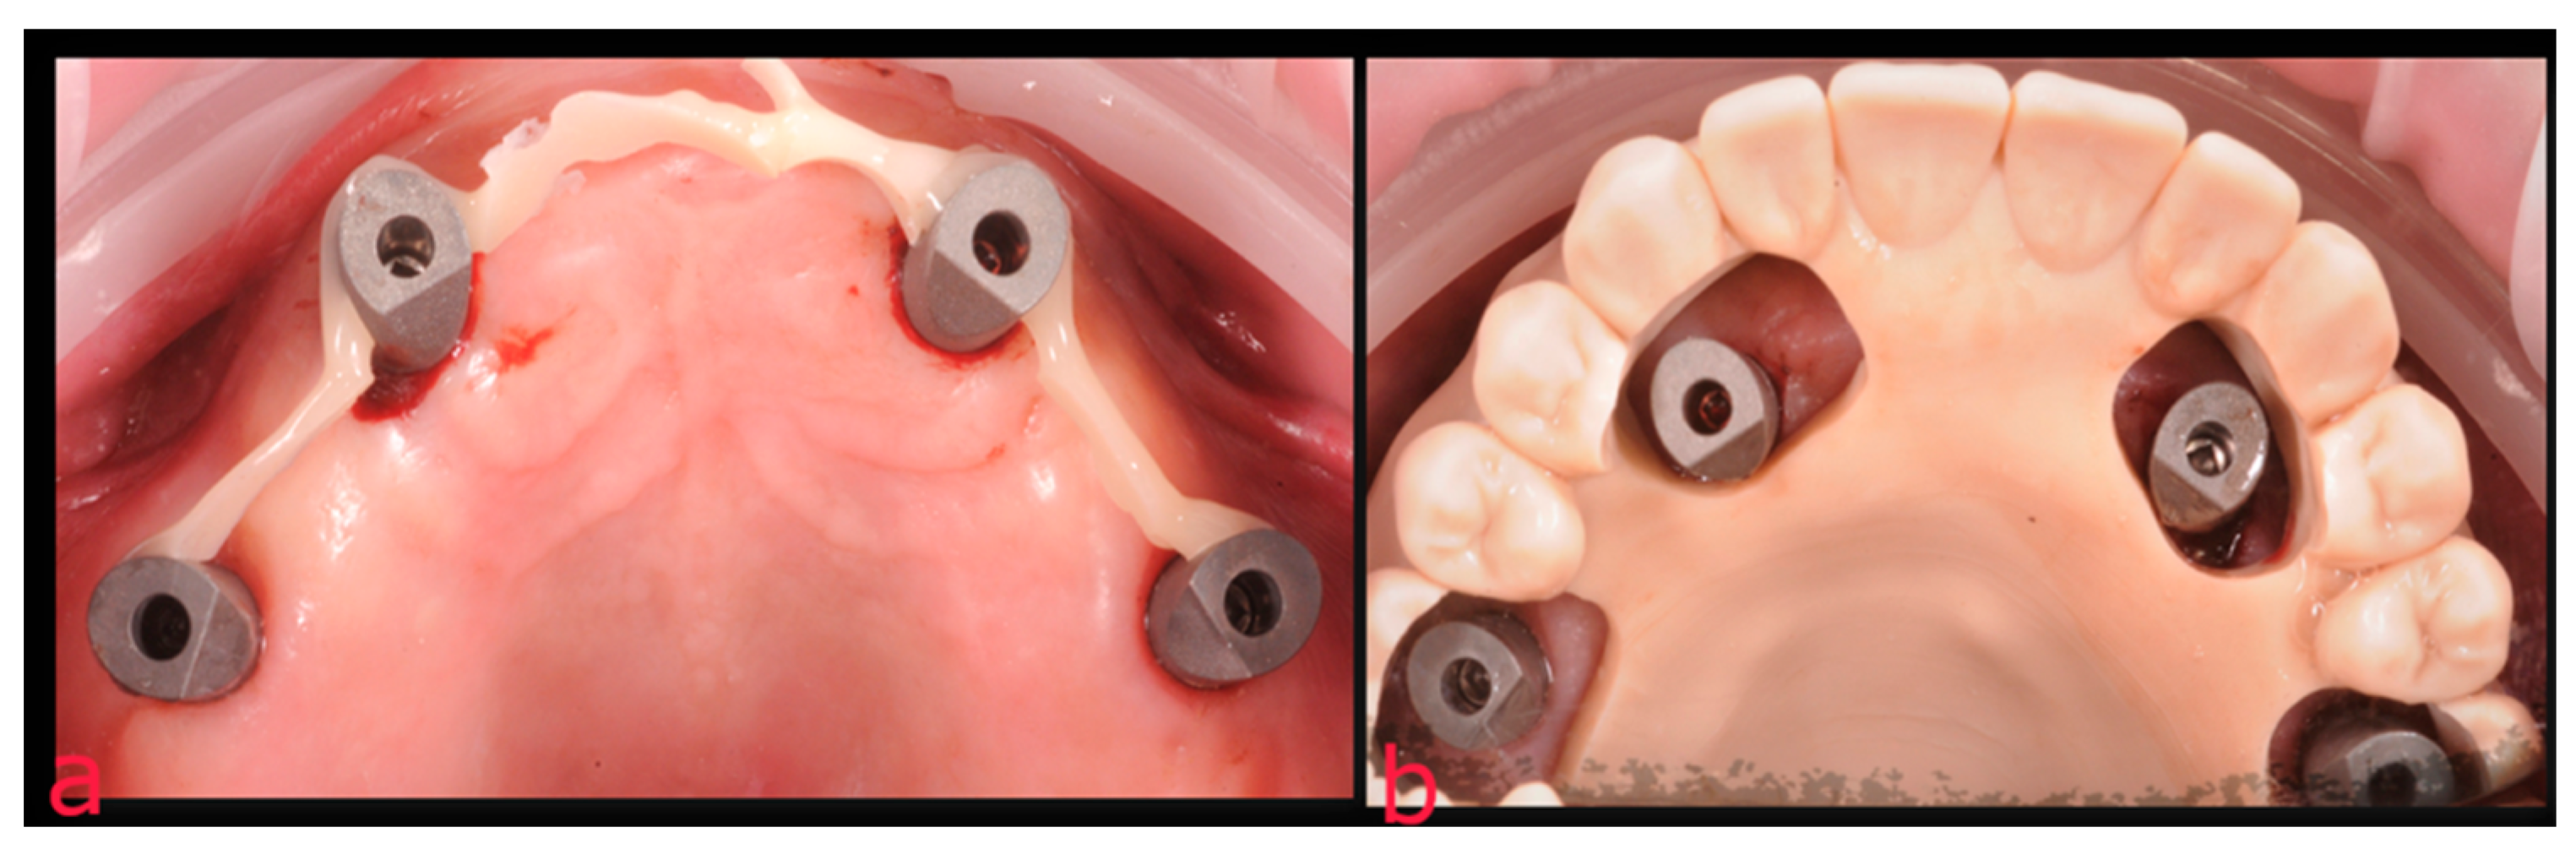

2.2. Second Step: From FDP to Implant-Supported Overdenture